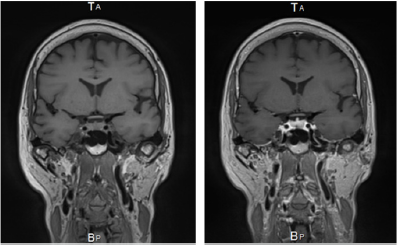

D. Diagnostic Imaging: MRI was done in several hospitals, but T1 image, T2 image, Flair, and MRA showed no abnormalities. However, coronal view of contrast-enhanced MRI that was taken first in Tokyo Rosai hospital showed thickening of the dura in the middle skull base with positive contrast enhancement. This finding was considered as hypertrophic pachymeningitis (Figure 1).

Figure 1: MRI scans with and without Gd. Lt side, coronal image T1, Rt side, coronal image of same position with Gd enhancement, linear dural thickening along bilateral middle fossa dura pointed out.

The headache in this case is exacerbated by reclining. It is speculated that this was caused by a decrease in hydrostatic pressure due to recumbency, resulting in a decrease in venous drainage of cerebrospinal fluid and an increase in intracranial pressure. Coronal image demonstrated linear dural thickening and enhancement along the middle cranial fossa shown in Figure 1. The middle cranial fossa dura matter is fed by meningeal arteries that are rich in sensory nerves from the trigeminal nerve. Unmyelinated nerve fibers derived from the trigeminal ganglion are distributed to the dural arteries and serve to transmit the noxious pain [2,3].